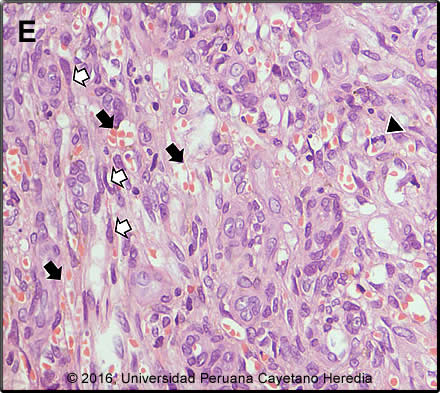

Diagnosis:Kaposi`s sarcoma (KS due to HHV8); HIV associated.

![]() Discussion: Biopsy of a skin lesion showed (Image E): microvascular proliferation (varying vessel shape and size with vascular congestion and RBC extravasation (black arrows); spindle cells (sarcomatoid cells) with pale eosinophilic cytoplasm and oval elongated nuclei (white arrows); occasional mitotic figures (arrow head). These 3 findings together are diagnostic of KS. CT scan of the chest (Image C) was read as showing multiple nodular lesions of different sizes located in both lungs and the CT scan of the abdomen (Image D) as showing hypondense lesions of the liver. GI endoscopy and colonscopy showed multiple violaceous lesions in the small and large intestine (images not available). Bronchoscpy did not show any endobronchial lesions and KOH, Grocott and ZN of the BAL were negative as were MGIT cultures for MTB and cultures for other mycobacteria. Latex agglutination test Cryptococcus was negative and histoplasma and paracoccidiodomycis immunodiffusion were negative. Culture for nocardia was negative. The differential diagnosis of the skin lesions in this patient includes mainly bacillary angiomatosis due to Bartonella; the biopsy helps in distnguishing these conditions, and a Waathin-Starry stain would indentify clumps of bacteria in bacillary angiomatosis. The differential diagnosis of pulmonary nodules in patients with HIV is broad and includes TBC, nocardia which is usually associated with skin lesions that look like nodules and abscesses, and fungal pathogens including histoplasma, paracoccidiodomycosis and cryptococcus Pneumocystosis rarely presents with nodules. Cancer including KS (the most likely), lymphoma, and metastatic cancer should also be considered. Kaposi’s sarcoma is caused by HHV-8 (human herpes virus 8) and was first described in Africa in the pre-HIV era. It is the most common HIV associated malignancy including in Latin America (J Acquir Immune Defic Syndr. 2011 April 15; 56(5): 467–473. doi:10.1097/QAI.0b013e31820bb1c3) and in some African countries with high HIV rates it is the most common malignancy in men. For unclear reasons though, it is uncommon in Asia. HHV-8 transmission routes are not totally clear and both sexual and horizontal nonsexual (mother to child; between siblings) HHV-8 transmission routes have been reported. Due to low general seroprevalence of HHV-8 in the population in developed countries and early initiation of anti-retroviral therapy, HIV-related KS is an infrequent condition in developed countries. Currently, KS is more commonly reported from developing countries than developed countries. HIV-infection is an important risk factor for developing KS in developing countries. HIV-infection is associated with an increased HHV-8 sero-prevalence in all population groups examined. Overall, HIV-positive persons are more likely to be HHV-8 seropositive than HIV-negative persons and the association is strongest in MSM, patients with hemophilia, and children (Int. J. Cancer: 138, 45–54, 2016). Co-infection with HIV and HHV8 is more frequent in males (reasons unclear), and is usually seen in severely immunosupressed patients, the lower the CD4 the higher the risk. Patients typically have a CD4< 200 cells/mm3 and history of an opportunistic infection such as pneumocystis. In patients who present with limited disease there is no indication to start chemotherapy; these patients will benefit from HAART (any regimen) alone (AIDS Reviews 7: 13-21, 2005). Clinically, this is a case of advanced poor-risk KS based on three criteria: 1) Tumor, T1 stage; 2) extensive disease that involves not only the skin but also mucosal membranes; 3) involvement of other non-lymph node viscera involved (lungs, GI tract and liver). Treatment of KS in HIV-infected patients depends on the stage of the tumor and number of skin lesions (this patient had less than 50) and presence of symptomatic disease. Considering the extensive involvement in this case and despite of the scarcity of symptoms chemotherapy was offered. 5-year survival in T1 disease has been approximated as 80% with HAART and chemotherapy but the extensive pulmonary disease in our patient speaks to a poorer prognosis in our experience. The standard of care in the developed world is liposomal anthracyclines (doxorubicin or daunorubicin), but these drugs are not available in most of the developing world (Cochrane Database of Systematic Reviews 2014, Issue 9. Art. No.: CD003256. DOI: 10.1002/14651858.CD003256.pub2). Alternatives are IV combination of vincristine + vimblastine, IV paclitazel or oral etoposide. The patient was started on paclitazel, as per local protocol, and ART (Atripla). |